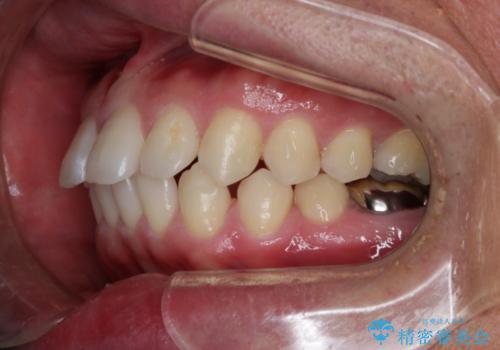

- 全体的に歯と歯の間に隙間があるのが気になるとのことで来院されました。インビザラインでの矯正治療をご希望されました。

隙間については、前歯と奥歯に多数あります。また、上下前歯は、外側に少し倒れているため隙間を閉じつつ、前歯を内側に引っ込めて並べることになりました。